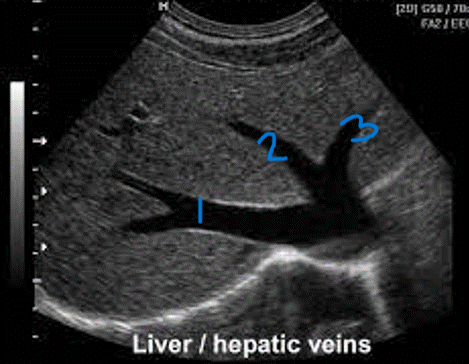

<p>In this sagittal plane, what is #1?</p>

In this sagittal plane, what is #1?

RHV

<p>In this sagittal plane, what is #2?</p>

In this sagittal plane, what is #2?

MHV

<p>In this sagittal plane, what is #3?</p>

In this sagittal plane, what is #3?

LHV